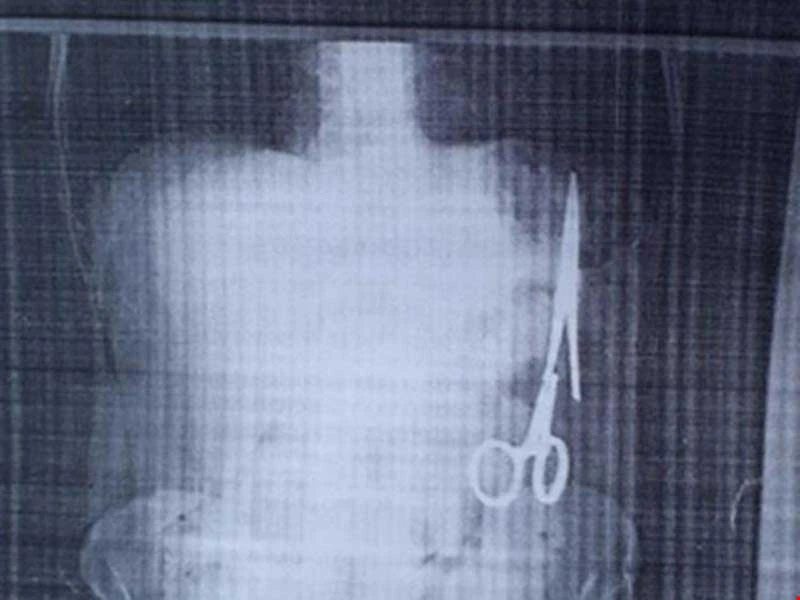

Bệnh nhân Ma Văn Nhật (54 tuổi, trú xã Bình Trung, huyện Chợ Đồn, Bắc Kạn) khi đi khám bệnh đã phát hiện ra trong ổ bụng có một chiếc kéo/panh dài 15 cm. Chiếc kéo này được cho là đã bị bỏ quên trong bụng bệnh nhân trong một ca phẫu thuật cách đây 18 năm tại BV Đa khoa tỉnh Bắc Kạn. May cho ông là chưa bị thủng ruột.

Chiếc kéo bị bỏ quên 18 năm trong bụng bệnh nhân Ma Văn Nhật.